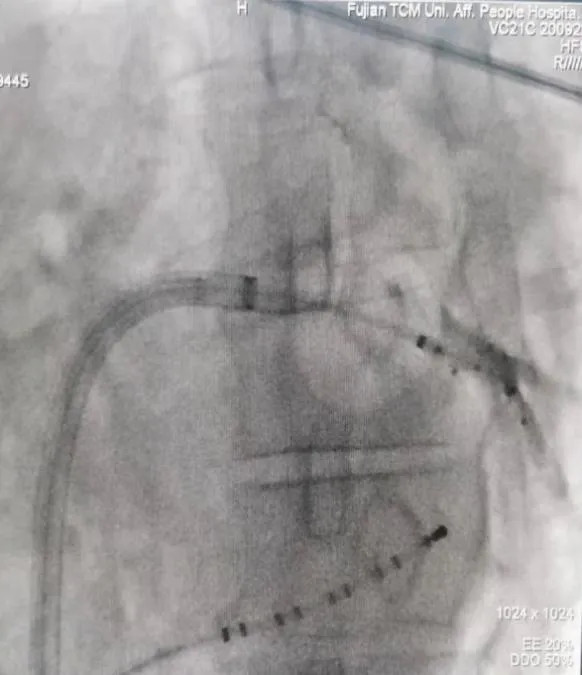

射頻消融術(shù)

三維電生理系統(tǒng)支持下的房性心動(dòng)過(guò)速射頻消融術(shù)

三維電生理系統(tǒng)支持下的心房顫動(dòng)+心房撲動(dòng)射頻消融術(shù)

房顫冷凍導(dǎo)管消融(陣發(fā)性房顫、高齡老人、心衰患者優(yōu)選)

長(zhǎng)程持續(xù)性房顫射頻消融術(shù)(環(huán)肺靜脈隔離+頂部線消融)

左心耳封堵術(shù)